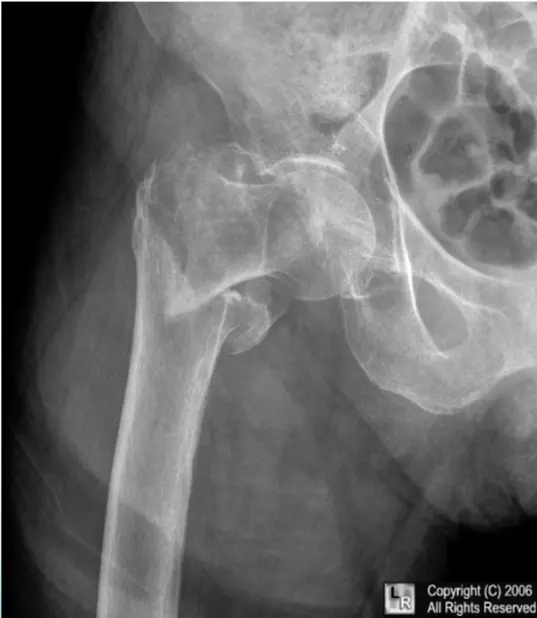

Patient: 46âyearâold lady

Incident: Fell two steps down the stairs and is now unable to stand.

Oncologic history: Breast carcinoma previously treated with chemotherapy and radiotherapy.

Fracture details

- Site: Upper shaft of the femur

- Type: Simple fracture

- Fracture line: Oblique crossing a lytic lesion â appears atypical

- Displacement: Medial shift with some overlap

- Special considerations: Pathological fracture related to metastatic disease

46âyearâold woman who slipped two steps down the stairs and was unable to stand.

She has a history of breast carcinoma treated with chemotherapy and radiotherapy.

- Location: Upper shaft of the femur

- Fracture line: Strange? (unusual pattern)

- Displacements:

- Medial shift

- Overlap

Special considerations: Pathological fracture (related to underlying disease).

Patient: 58âyearâold woman who fell at home and now has rightâhip pain with inability to walk.

Site â neck of the right femur (intraâcapsular).

Fracture type â simple, transverse line.

Displacement â varus, with the femoral head angled downward.

Special concerns â high risk of avascular necrosis (AVN) because the fracture is intraâcapsular.

- Site: intertrochanteric

- Type: comminuted

- Fracture line: multiple

- Displacements: varus / overlap

- Special issues: osteoporosis, unstable fracture, no AVN

- Site: NeckâŻLtâŻfemur â intraâcapsular

- Type: Simple

- Fracture line: Transverse

- Displacements: Valgus / impaction

- Special issues: Stable; has vascular clips; AVN depends on age